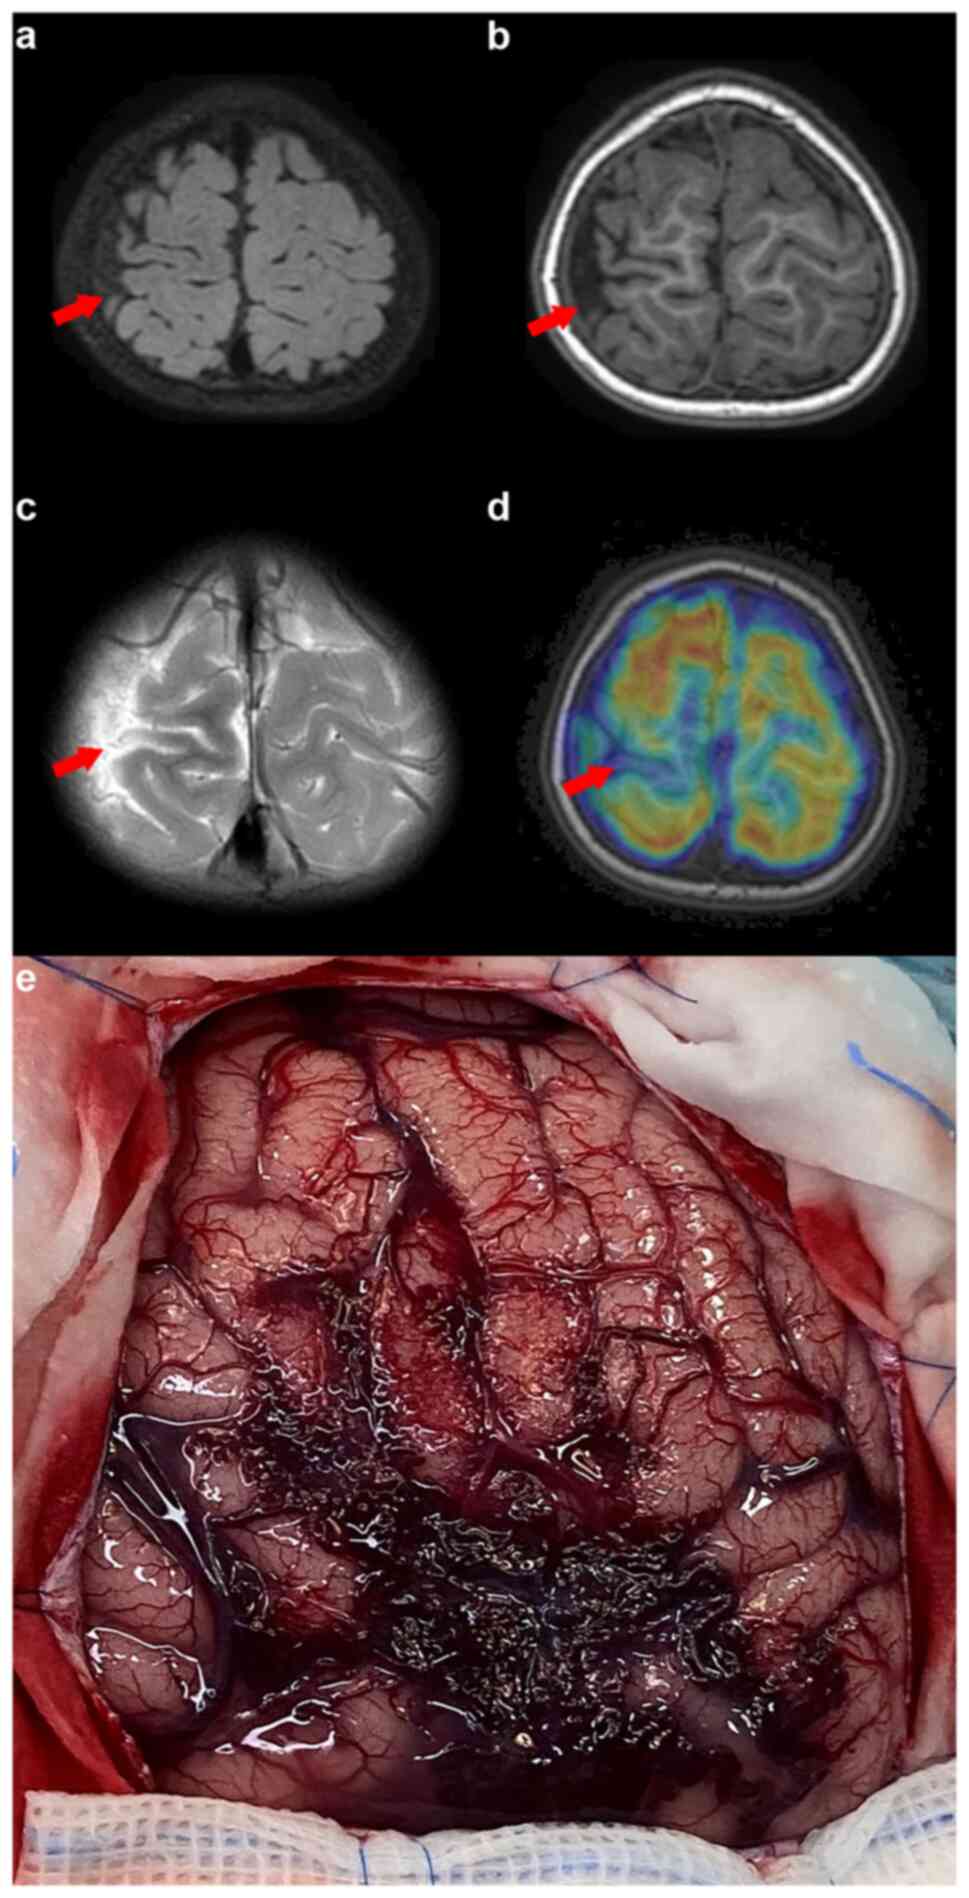

Radiological evaluation using magnetic resonance imaging (MRI) revealed a marginally reduced left frontal-parietal lobe compared with the right parietal lobe, abnormal local myelination and a size disparity in the A1 segment of the left anterior cerebral artery. Notably, a venous malformation in the left frontal region and numerous small, winding superficial veins in the left subarachnoid space were observed (Fig. 1). An electroencephalogram (EEG) indicated slow background activity with left-right asymmetry and slow-wave discharges, sometimes classified as periodic lateralized epileptiform discharges, from the anterior and temporal head regions, pinpointing a focal epileptic episode on the right side (Fig. 2).

Figure 1

Brain MRI showcasing the discrepancy in size between the left and right frontal-parietal lobe. (a) Discrepancy in size between the left frontal-parietal lobe and its right counterpart on skull MRI. (b) Visualization of left pia mater and venous malformations. (c) Evidence of localized structural asymmetries and abnormalities. The red arrow indicates the lesion.

Upon presentation at the hospital, the patient was preliminarily diagnosed with epilepsy. Despite oxcarbazepine (210 mg every 12 h, orally) and perampanel treatment (3 mg nightly, orally), the seizure patterns changed, involving abrupt shakes, falls and limb tremors. No significant personal, familial or prior health issues were reported. A physical assessment revealed a conscious yet minimally responsive patient with bilateral muscle strength grade V. An EEG showed generalized or right focal myoclonic-atonic seizures (Fig. 3). MRI, MR angiography and MR venography indicated a smaller right parietal gyrus portion and localized cortical dysplasia, with multiple enhanced vascular shadows in the right parietal space suggesting vascular malformation (Fig. 4). A preoperative evaluation, including positron emission tomography (PET)/CT and skull MR fusion, localized an epileptogenic focus in the right central parietal area, indicative of focal cortical dysplasia (FCD). A craniotomy performed to resect the epileptic focus revealed a vascular mass flexion in the right parietal region. The clinical and surgical findings led to a diagnosis of SWS type III (Fig. 4). Post-surgery, the patient was enrolled in a detailed follow-up program, including visits at ~1, 3, 6 and 12 months, to closely monitor recovery and seizure activity. Over the 1-year follow-up period, the patient experienced a stable recovery and remained seizure-free. This follow-up regimen facilitated the early detection and management of any potential complications, contributing to the patient's positive prognosis. The continued absence of seizures post-surgery underscores the effectiveness of the surgical treatment and supports a favorable outlook for the patient's continued neurological health.

Figure 4

Brain magnetic resonance imaging and intraoperative image detailing abnormalities in the right parietal lobe. (a) Diminished size of the right parietal gyrus with evidence of local cortical dysplasia. (b) Enhanced vascular shadows suggesting multiple disorders in the right parietal space, pointing to vascular malformations. (c) Positron emission tomography-computed tomography scan revealing a low metabolic signal in the right posterior central gyrus. (d) Intraoperative visual field capturing a vascular mass in the right parietal area. (e) Vascular malformation in the right parietal region shows a complex network of enlarged and intertwined vessels that appear redder or sometimes deep blue, reflecting the oxygenation status within these abnormal vessels. The irregular shape of the vascular malformation is evident, with intricate paths through brain tissue clearly discernible. Surrounding the malformation, there may be signs of tissue atrophy or damage. The red arrow indicates the lesion.